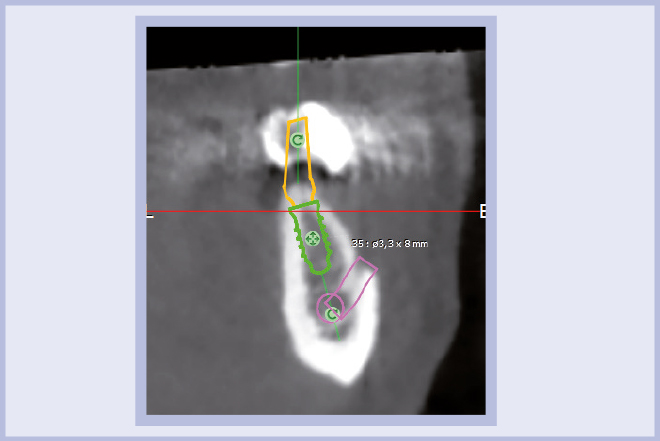

Per riabilitare la masticazione del terzo quadrante, con osso gravemente atrofico, si procede allo studio del caso con esame radiologico 3D e posizionamento virtuale di impianti Exacone® Leone. La prima valutazione è stata eseguita con il software dell’apparecchio radiografico Cone Beam presente in studio. Dopo aver verificato che la quantità di osso residuo fosse sufficiente all’inserimento di due impianti, seppur di dimensioni ridotte, in sede 3.5 e 3.6 senza l’ausilio di tecniche di rigenerazione ossea (Figg. 1-3), si richiede al laboratorio di confezionare una mascherina radiologica con ceratura diagnostica radiopaca e repere standardizzato a livello incisale come da protocollo Leone (Figg. 4, 5). Si verifica quindi clinicamente l’assenza di mobilità della mascherina dopo il posizionamento nel cavo orale del paziente (Figg. 6, 7). Si effettua una CBCT con la mascherina in posizione e l’esame viene inviato in formato DICOM all’azienda Leone assieme al modello master della paziente. L’azienda provvede quindi ad inviare agli Autori il software 3Diagnosys (software di progettazione) in licenza monopaziente con caricati i file DICOM ricevuti; il software viene quindi utilizzato per la progettazione definitiva del caso (Figg. 8-12).

- Figg. 1-3 – Esame Cone Beam iniziale, si verifica la fattibilità di inserimento impianti

- Fig. 2 mento impianti

- Fig. 3

- Figg. 8-12 – Pianificazione implantare con software 3Diagnosys Leone

- Fig. 9

- Fig. 10

- Fig. 11

- Fig. 12